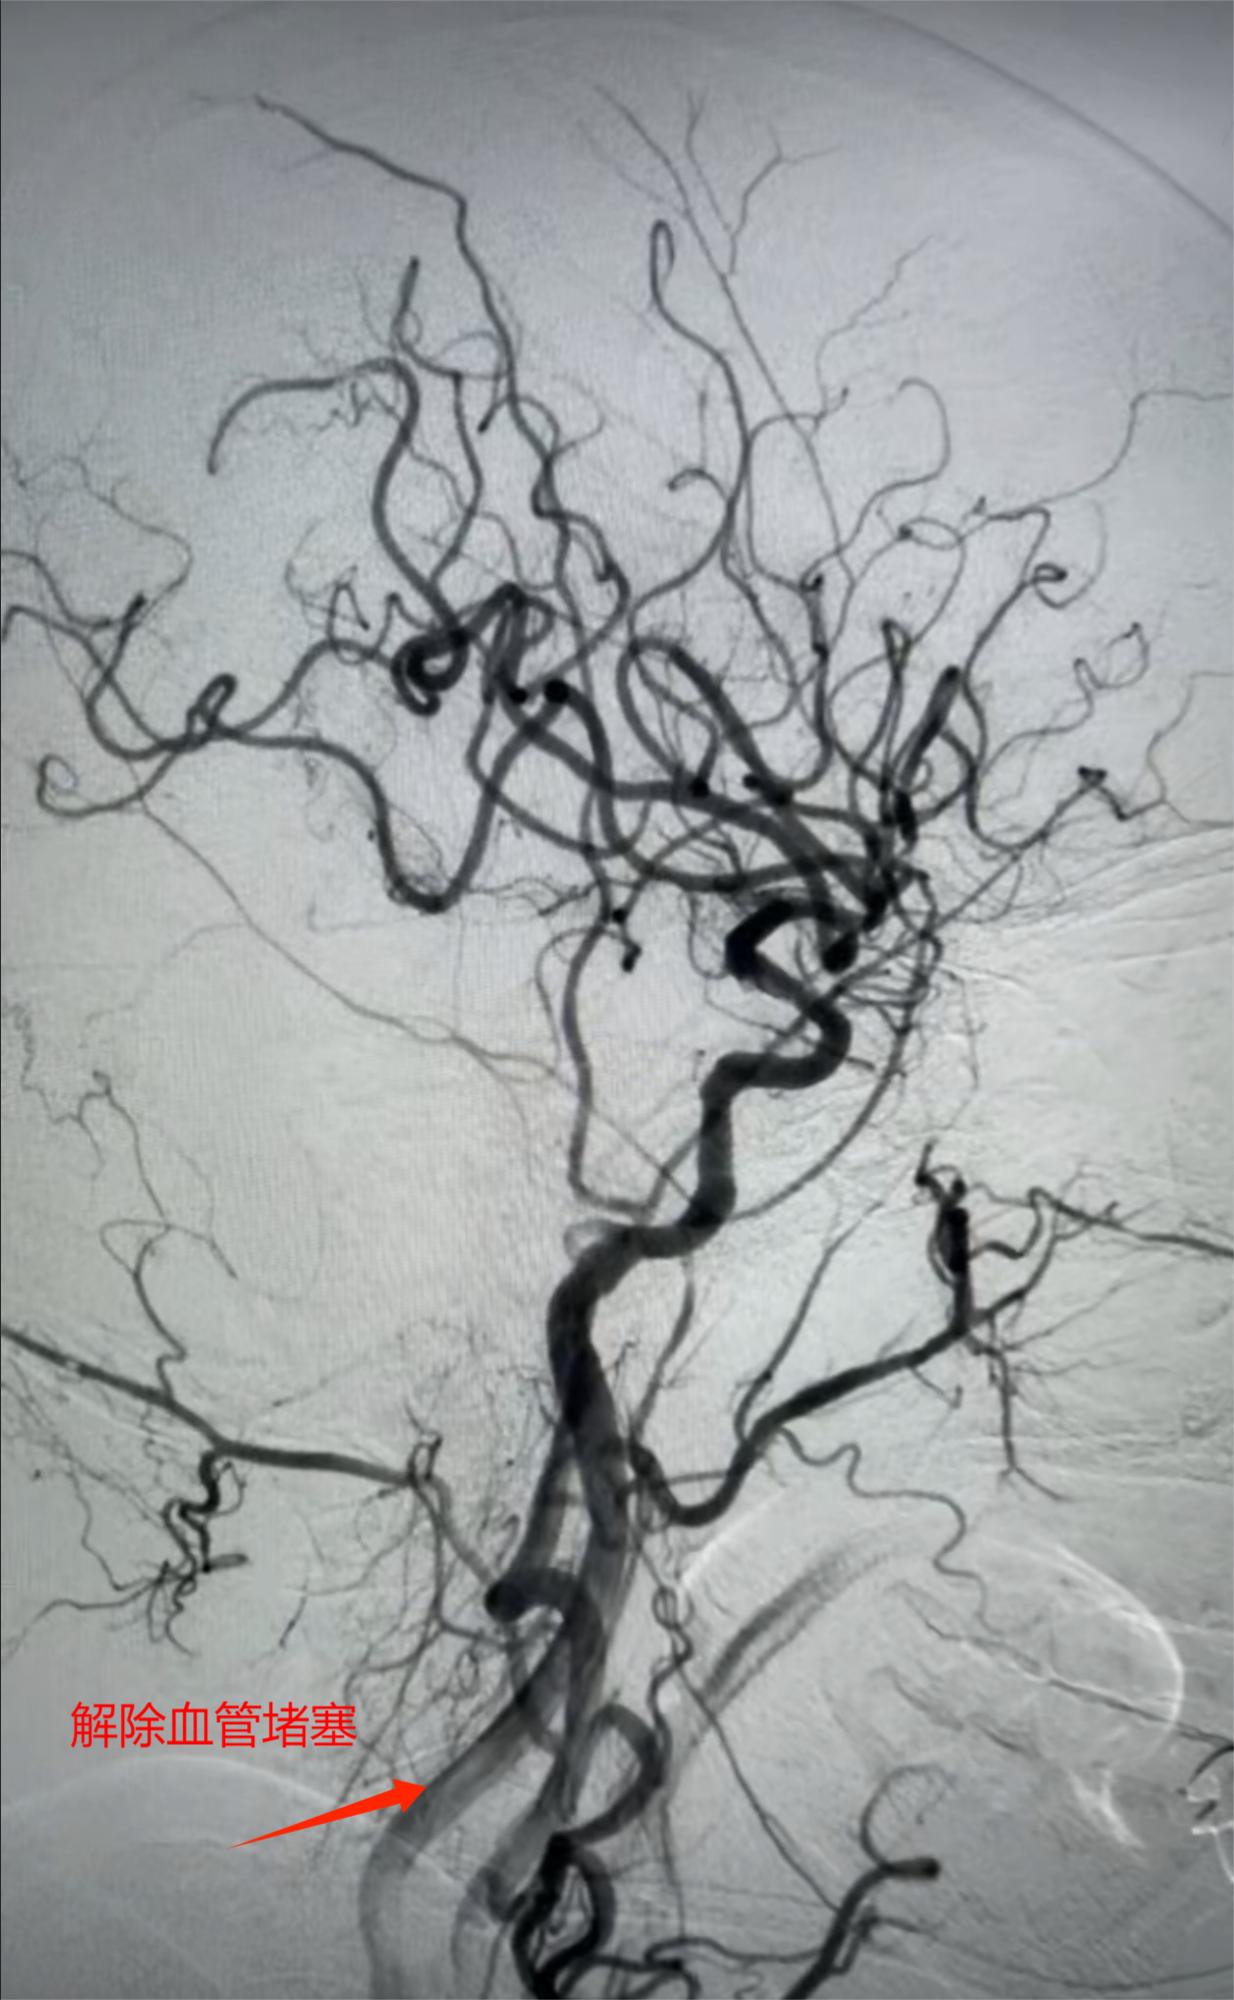

在局麻下,神经内科介入团队行脑血管造影,精准定位闭塞部位。随后实施“经皮颅内动脉取栓术”,成功取出堵塞血管的血栓。术中发现患者颈内动脉颅内段存在重度狭窄,团队立即施行“经皮颈内动脉颅内段球囊扩张成形术+经皮颅内动脉支架置入术”,彻底解除血管狭窄,重建脑血流。

从入院至血管再通全程控制在60分钟内,远低于国际指南推荐的90分钟标准,为大脑功能的恢复赢得了最关键的时间。